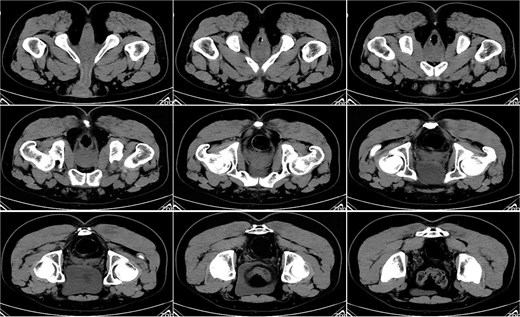

On postoperative Day 7, the patient developed a fever (38.5°C) and mild lower abdominal discomfort. Laboratory tests revealed leukocytosis (white blood cell count: 16.06 × 109/l, neutrophil percentage: 89.1%). A pelvic computed tomography (CT) scan suggested cystitis (Fig. 1). Anti-infective therapy with intravenous cefoperazone sodium and sulbactam sodium was initiated. The patient’s vital signs, complete blood count, and temperature were closely monitored.